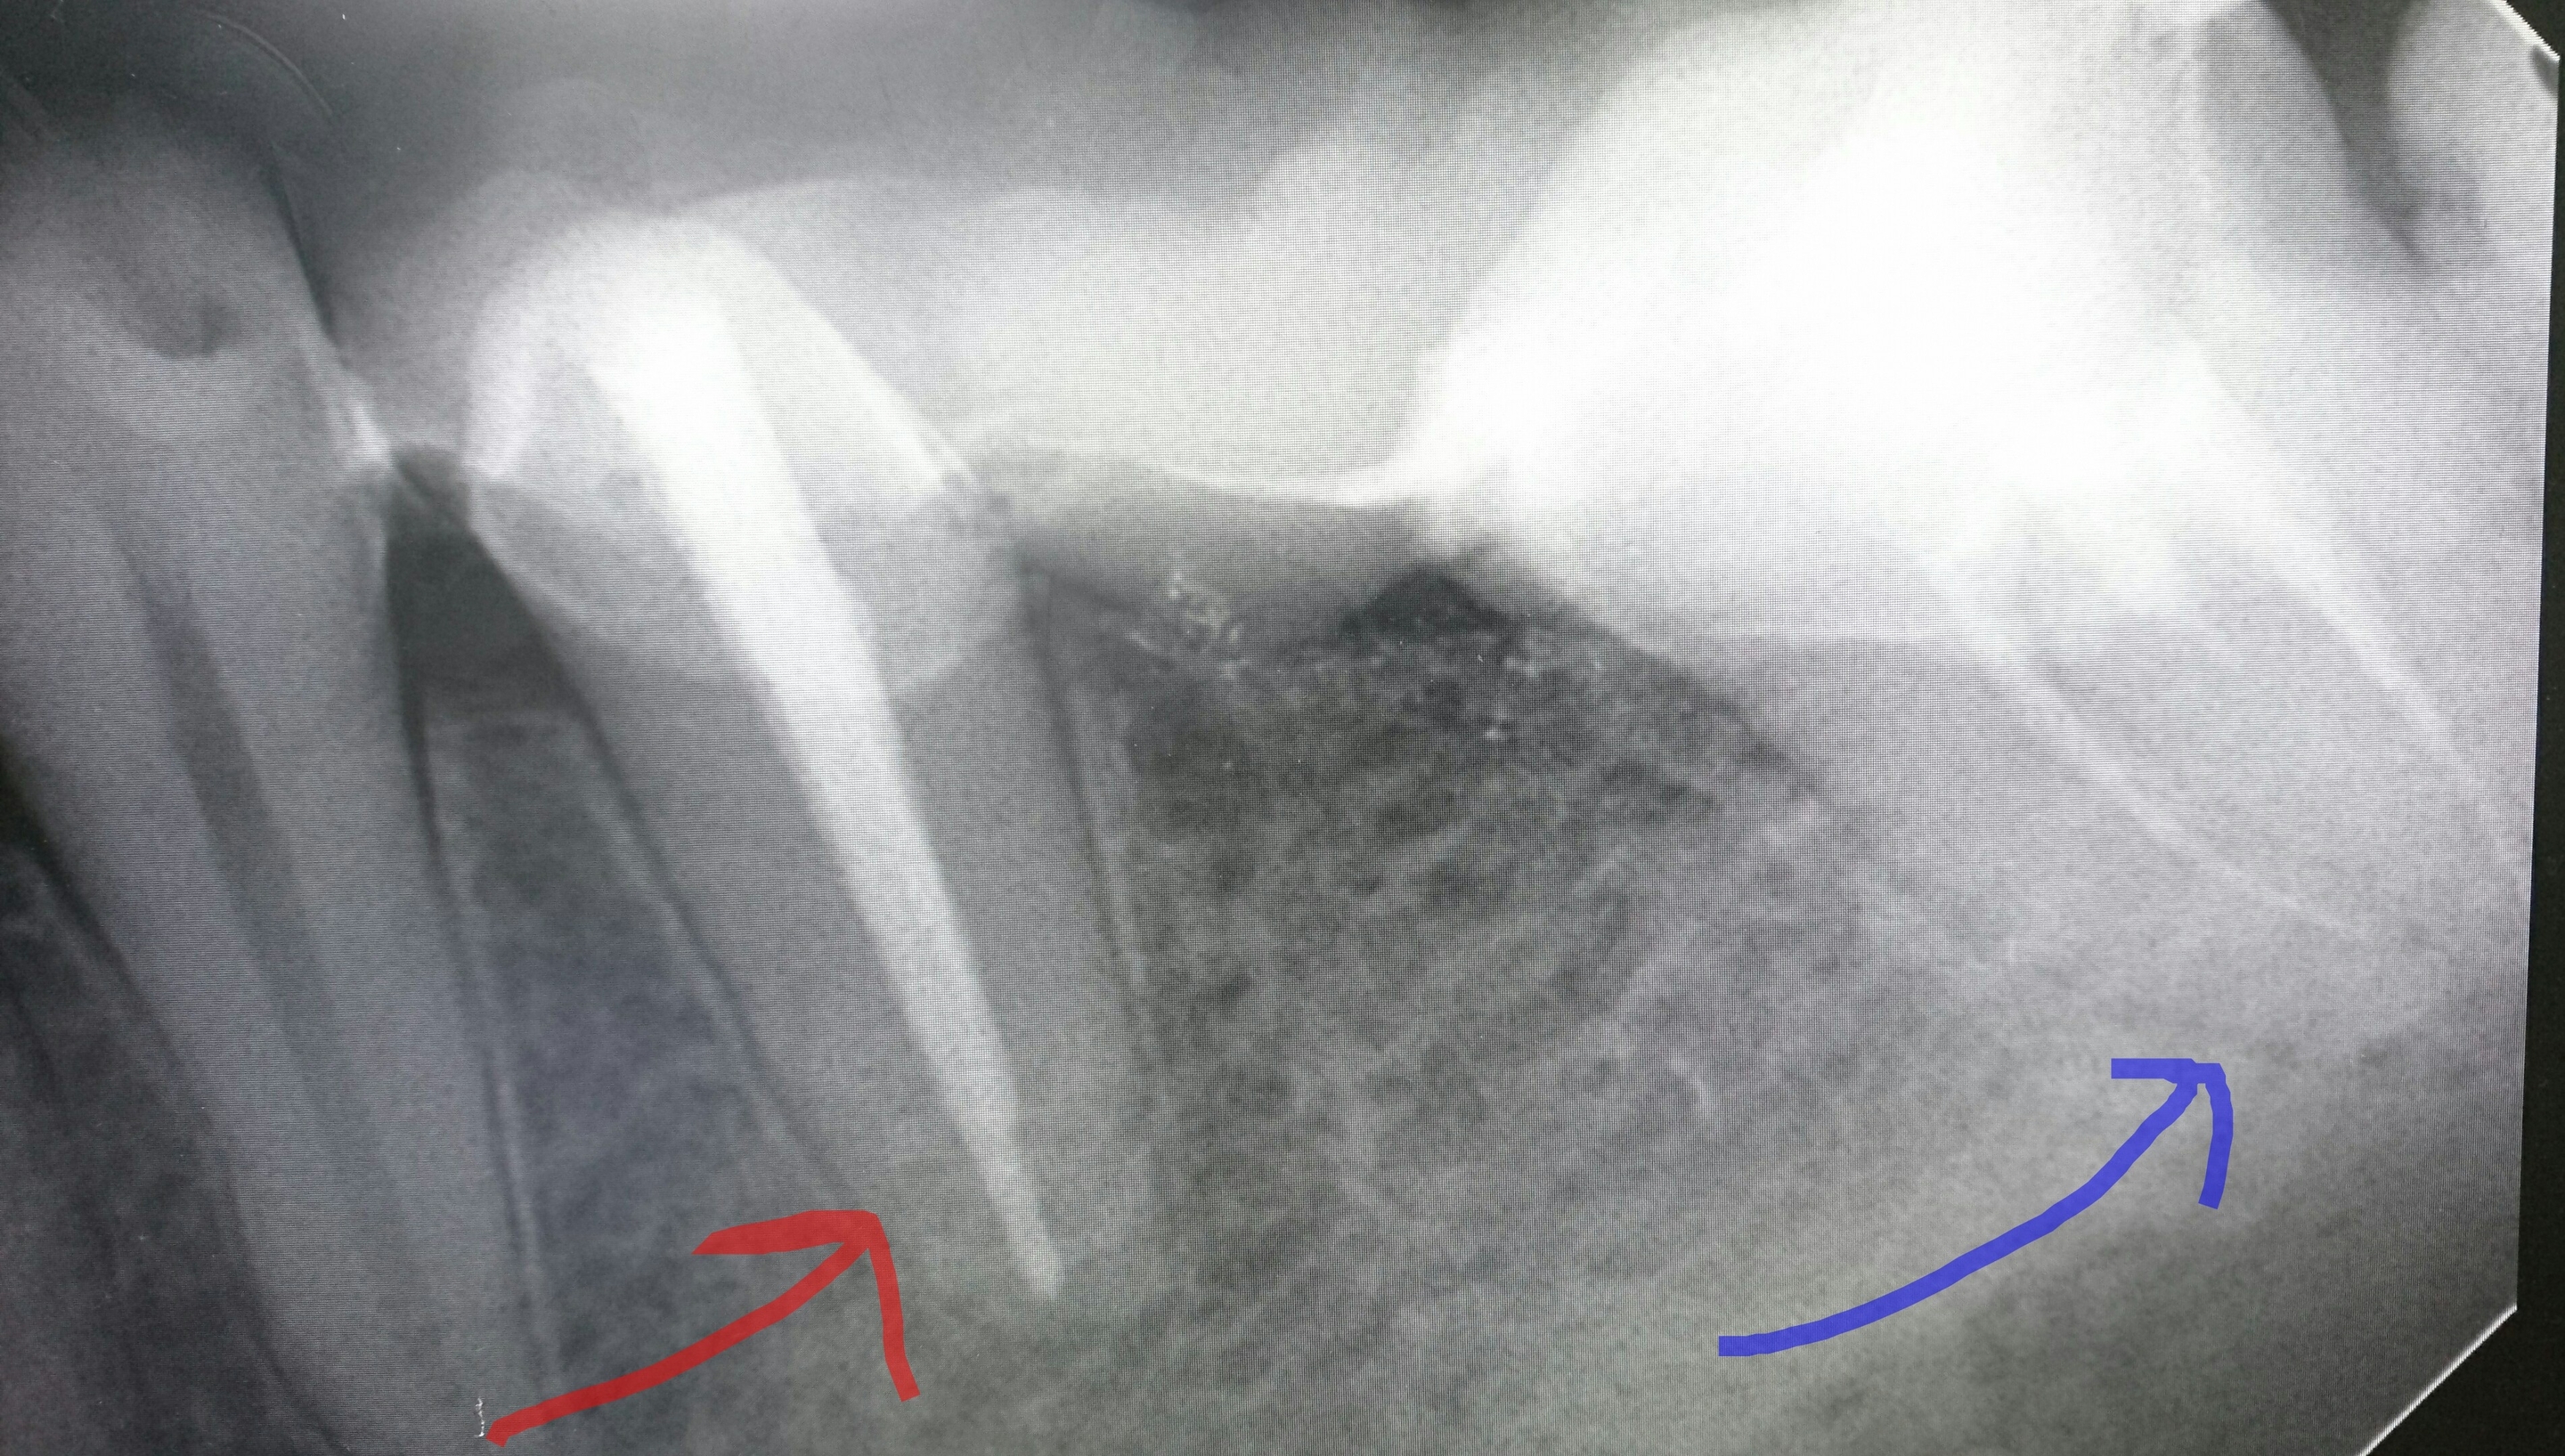

根治左赤→1根充、右青→3根充にて根の治療終了❗

根治左::3根管根充後 右:3根管を器具で明示❗根充赤○奥歯の根充後❗その下には親知らずが水平に埋伏。悪さをしないと良いのですが・・・❗この親知らずが抜歯となるととても難しい抜歯になりますから。根充奥歯の根充後❗根治終了❗根充根充後❗赤○に膿(歯根嚢胞)が貯留しているため(CTにて確認済)関東労災病院にて外科的切除を依頼した症例。